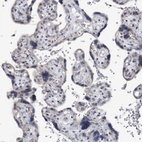

Immunohistochemical staining of human thyroid gland shows strong cytoplasmic positivity in glandular cells.